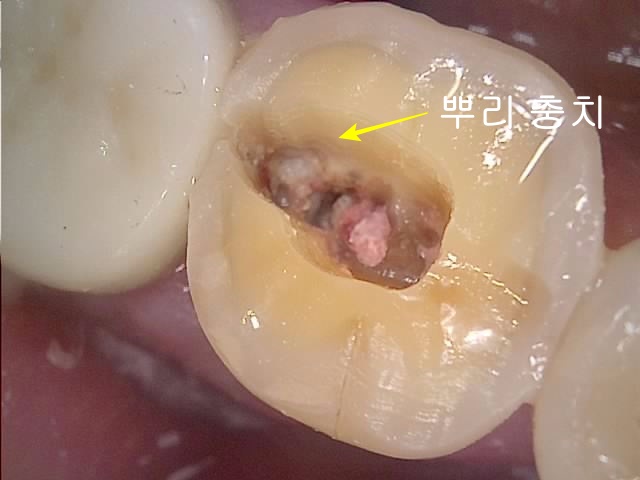

STEP 1: 깊은 충치 제거 및 격리(Isolation)

가장 먼저 진행된 것은 잇몸 하방 깊은 곳까지 진행된 충치를 제거하는 것입니다. 충치를 제거하고 나면 치아 내부 깊은 곳까지 뚫려 있는 것을 볼 수 있습니다.

이때 가장 중요한 것이 바로 **’격리(Isolation)’와 ‘벽(Wall) 쌓기’**입니다.

- 타액 및 세균 차단: 신경치료 중 침이나 피가 들어가지 않게 잇몸체로부터 치아 내부를 완벽히 격리해야 합니다.

- G.I Wall 형성: 빈틈(Leakage)이 생기면 소독약이 새어 나가거나 입안 세균이 신경관을 오염시켜 치료 실패의 원인이 됩니다. 따라서 빈틈없이 벽을 쌓는 이 과정(Building Wall)은 고도의 기술을 요하는 매우 중요한 단계입니다.